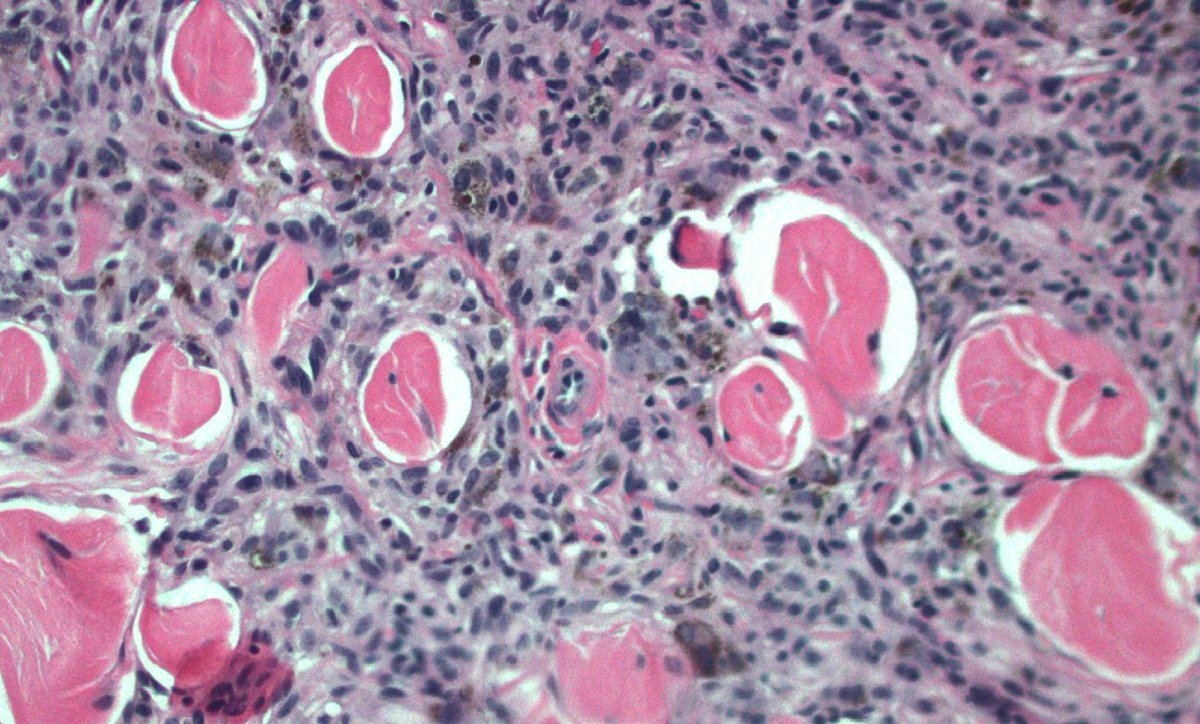

40 F. 10 cm deep thigh mass.

Answer ✅ youtu.be/QDb68_G1HR4?si…

Digital slide 🔬 kikoxp.com/posts/11800.

Differential dx: kikoxp.com/posts/12124

#BSTpath #pathologists #pathology #pathTwitter